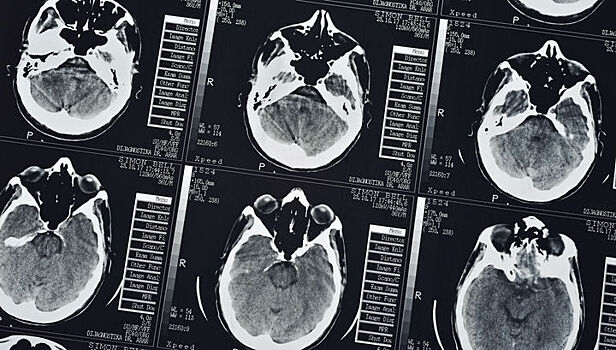

Учёные успешно применили протезную систему памяти, чтобы помочь людям вспомнить информацию, которую иначе они просто не запомнили бы. В пресс-релизе Баптистского медицинского центра Уэйка Фореста отмечается, что специалисты продемонстрировали успешную работу протезной системы, использующей собственные паттерны (шаблоны) памяти людей, чтобы облегчить способность мозга кодировать и вспоминать информацию. Исследование является важнейшим шагом на пути к созданию способа восстановления памяти. Новая система помогла участникам исследования повысить эффективность кратковременной памяти на 35-37 процентов. Исследование было сосредоточено на улучшение эпизодической памяти, сообщают авторы работы. Поясним, что речь идёт об информации, которая является для человека новой и полезной лишь на протяжении короткого периода времени (где припаркована машина, куда положили очки). А долговременная память хранит данные, использующиеся в течение более длительного времени (например, то, что изучалось в школе). Именно с этой эпизодической памятью чаще всего возникают проблемы у людей с болезнью Альцгеймера, перенёсших инсульт или получивших травму головы. Исследователи работали с пациентами с эпилепсией, находящихся в Баптистском медицинском центре Уэйка Фореста. Эпилепсия часто приводит к потере памяти. Кроме того, такие пациенты часто становятся объектами исследований интерфейса мозг-компьютер, поскольку в рамках своей терапии они уже могут быть подключены к электродам. Проще говоря, такие люди участвовали в диагностической процедуре картирования мозга. Процедура использует хирургически имплантированные электроды, размещённые в различных областях мозга, чтобы точно определить первопричину припадков людей с эпилепсией. Так и в данном исследовании учёные хирургически имплантировали электроды для фиксирования нейронной активности в областях гиппокампа. Они сфокусировались на гиппокампе, поскольку он, как известно, участвует в консолидации памяти (то есть перехода кратковременной памяти в долговременную). Электроды были имплантированы точно в две области гиппокампа, которые поддерживают кодирование и извлечение информации. В пресс-релизе отмечается, что учёные использовали электронную протезную систему, основанную на нелинейной математической модели MIMO. Они влияли на особые паттерны нескольких нейронов в гиппокампе. Сначала они записывали нейронные паттерны, или "коды", во время выполнения участниками компьютеризованного задания по проверке памяти. Участникам эксперимента показывали простое изображение (скажем, цветной кубик), а затем ненадолго убирали его с экрана. Спустя короткое время людям показывали уже серию снимков, и среди них было первое изображение. Задача – вспомнить, какое изображение показывалось изначально. Затем специалисты проанализировали записи правильных ответов и синтезировали код, основанный на MIMO, для правильной работы памяти. Далее учёные воспроизвели этот код пациентам, пока те выполняли задания, направленные на воспоминания данных. В этом испытании результативность эпизодической памяти улучшилась на 37 процентов по сравнению с исходными данными. Во втором тесте участникам показывали снимок, а после короткого перерыва просили найти его среди серии других. Подобные испытания проводились с разными снимками, а во время процедуры учёные фиксировали нейронные паттерны, чтобы определить и доставить "коды" правильного ответа. Позже учёные показали пациентам набор из трёх изображений в одно и то же время (там были старые и новые снимки). Участников эксперимента на этот раз просили определить снимки, которые они видели за 75 минут до этого. Стимуляция "кодов" правильного ответа помогла добровольцам на 35 процентов улучшить память. Хотя система не может заменить процесс формирования памяти, она даёт надежду, что в будущем миллионы людей с деменцией смогут вновь вспомнить простые, но вместе с тем важные вещи: где они живут, лица родных и так далее. "Впервые учёные смогли определить собственный "код" клеток мозга человека, или паттерн для памяти, и по сути вписать этот код, чтобы улучшить существующую память. Перед нами первый шаг к возможному восстановлению памяти, — говорит ведущий автор исследования Роберт Хэмпсон (Robert Hampson). — Мы показали, что можем использовать собственное содержимое памяти человека, чтобы укрепить её и вернуть пациенту". Отмечается, что исследование финансировалось Управлением перспективных исследовательских проектов Министерства обороны США (DARPA) как часть проекта "Восстановление кратковременной памяти" (Restoring Active Memory), запущенного ещё в 2013 году. Цель программы состоит в создании имплантируемого интерфейса мозг-компьютер, способного восстановить функцию памяти у людей, страдающих от травмы головы или различных заболеваний. "Мы хотим, чтобы это исследование стало основой для разработки, помогающей восстанавливать функцию памяти у людей, которые страдают от ухудшения памяти из-за травмы или болезни", — заключает Хэмпсон. Исследование нельзя назвать масштабным, и оно всё ещё находится на ранней стадии, однако результаты работы значительны. Возможно, в один прекрасный день исследование поможет восстановить утраченные способности мозга. Ранее авторы проекта "Вести.Наука" (nauka.vesti.ru) рассказывали, что тревожность может улучшить память человека. Также сообщалось о мозговом имплантате, который помог пациентам замедлить развитие старческого слабоумия.